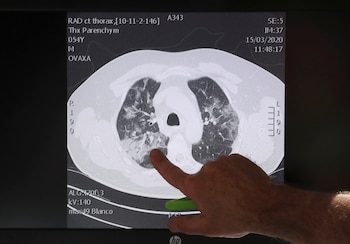

Otros modelos, como el de Alibaba, trabajan sobre imágenes de tomografías computadas: el algoritmo de IA del gigante tecnológico chino distinguió con un 96% de confiabilidad la neumonía común de la causada por el nuevo coronavirus, según un informe de Nikkei Asian Review. Y sólo demora 20 segundos.

Este desarrollo del instituto de investigación de Alibaba, Damo Academy, comenzó por entrenar el modelo de IA con datos de muestras de más de 5.000 casos confirmados. Se probó en el nuevo Hospital Qiboshan de Zhengzhou, en la provincia de Henan, que se hizo a partir del modelo del Hospital Xiaotangshan de Beijing, erigido en 2003 durante la crisis del síndrome respiratorio agudo grave (SARS), y se llevó a más de 100 instituciones médicas en las provincias de Hubei, Guangdong y Anhui.